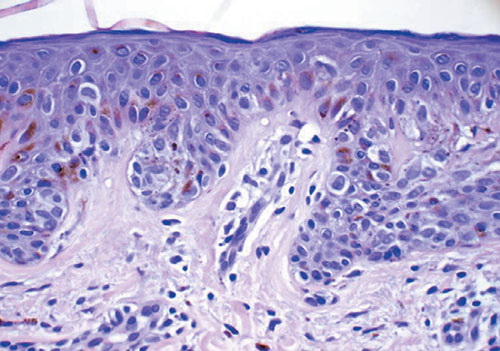

Atypical compound (dysplastic) nevus =وحمة مركبة عسيرة التصنع غيرنموذجية